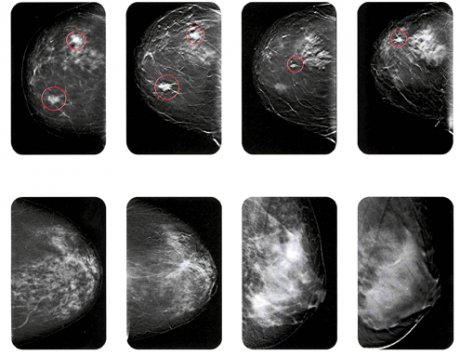

Mammografia 3D migliora lo screening senologico

Insieme a quelle convenzionali in due dimensioni, le mammografie 3D offrono sostanziali miglioramenti nella rilevazione del cancro riducendo i falsi positivi.